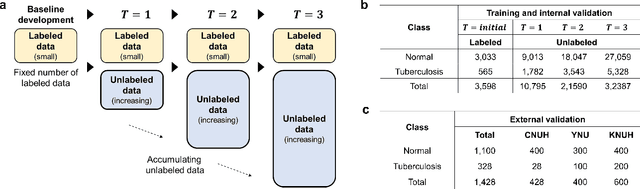

Abstract:Although deep learning-based computer-aided diagnosis systems have recently achieved expert-level performance, developing a robust deep learning model requires large, high-quality data with manual annotation, which is expensive to obtain. This situation poses the problem that the chest x-rays collected annually in hospitals cannot be used due to the lack of manual labeling by experts, especially in deprived areas. To address this, here we present a novel deep learning framework that uses knowledge distillation through self-supervised learning and self-training, which shows that the performance of the original model trained with a small number of labels can be gradually improved with more unlabeled data. Experimental results show that the proposed framework maintains impressive robustness against a real-world environment and has general applicability to several diagnostic tasks such as tuberculosis, pneumothorax, and COVID-19. Notably, we demonstrated that our model performs even better than those trained with the same amount of labeled data. The proposed framework has a great potential for medical imaging, where plenty of data is accumulated every year, but ground truth annotations are expensive to obtain.